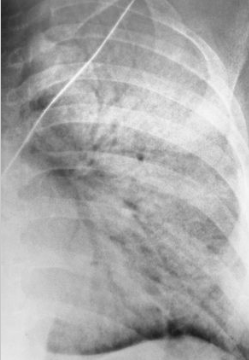

PT is 43 yr old male presenting with productive cough and fever/chills

What pathology is present?

pneumonia — alveolar/pneumococcal pattern